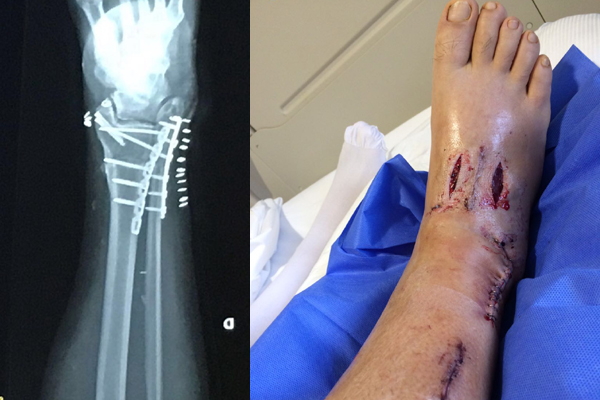

Vale recordar que 17 de agosto Andaur tuvo que ser operado al sufrir una fractura en un pie mientras jugaba un partido de fútbol. Este procedimiento se complicó y en vez de durar las dos horas pauteadas inicialmente, se terminó convirtiendo en dos operaciones que duraron 14 horas.

Todo debido a que sufrió tres trombosis arteriales y una venosa, algo que lo tuvo cerca de necesitar una amputación porque no existía irrigación sanguínea a una de sus piernas. Debido a ello, durante la operación se le tuvo que practicar una una osteotomía (corte quirúrgico), en la tibia. Además, Andaur explica que "tuvieron que cortarme una artería y hacer un bypass porque se había cortado la circulación".

"Estoy con tratamiento anticoagulante. Tenía 30 mg diarios y los bajé a 20 en menos de un mes. En cuanto al rango articular, cuenta que tras la operación mejoró: "Tengo el pie más flexible. Antes había tenido una fractura expuesta en el mismo lugar y mi pie se movía en un 70% del rango, pero ahora se mueve en un 100 por ciento. La operación permitió que arreglaran todo, así que estoy súper optimista". En cuanto al proceso agrega: "Voy súper bien, más adelantado de lo normal".